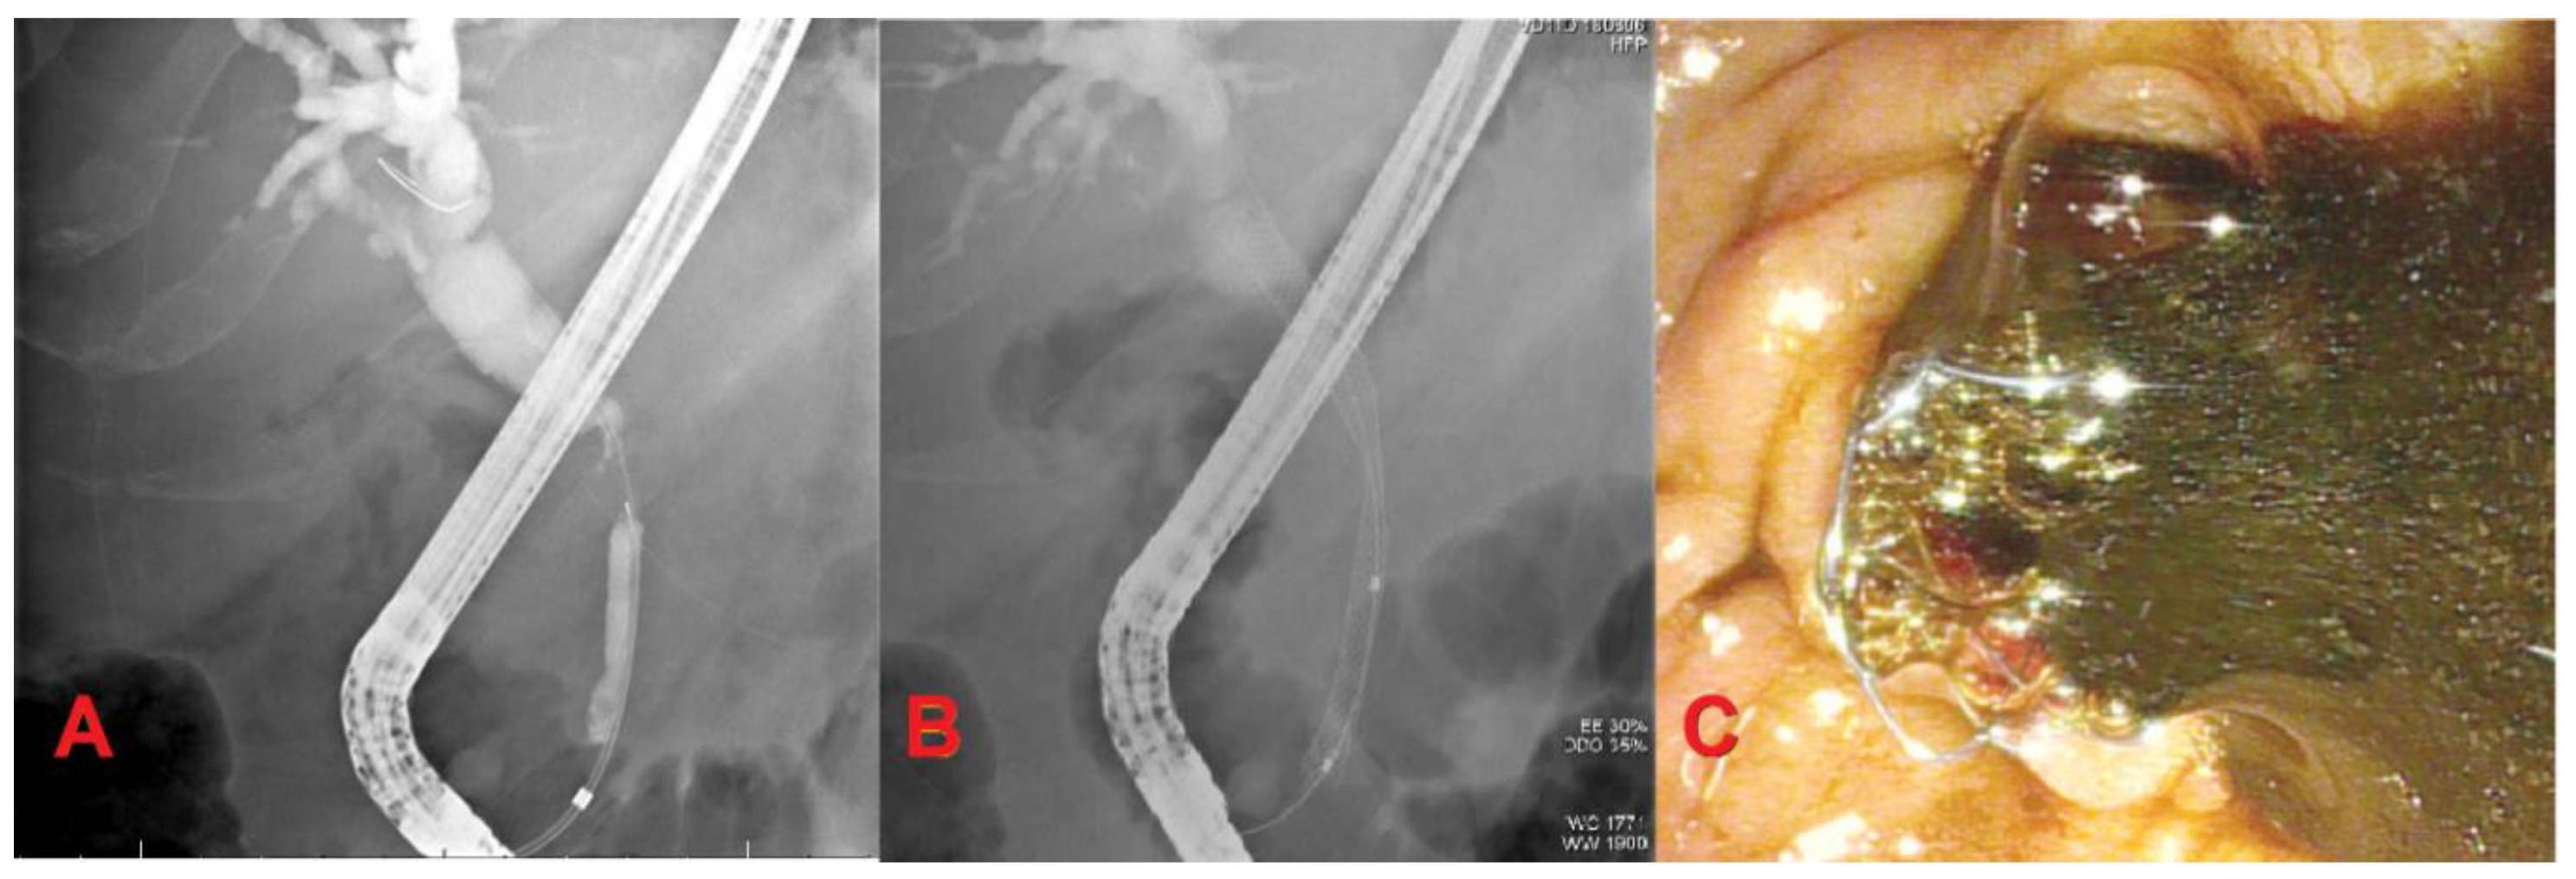

Self-expandable metallic stents can be uncovered (UCSEMS), partially covered, or fully-covered (FCSEMS). UCSEMS are less prone to migration, but are difficult to remove due to tissue ingrowth. FCSEMS have a nonporous membranous coating designed to decrease rates of occlusion with easy removability. However, this benefit comes at the expense of increased risk of stent migration [15] (Figure 1).

Figure 1.

Extrahepatic cholangiocarcinoma. (A) Mid-common bile duct stricture with dilation of proximal bile duct and intrahepatics; (B) Fully-covered self-expandable metallic stent (FCSEMS) placement for biliary drainage; (C) Bile drainage after FCSEMS placement.